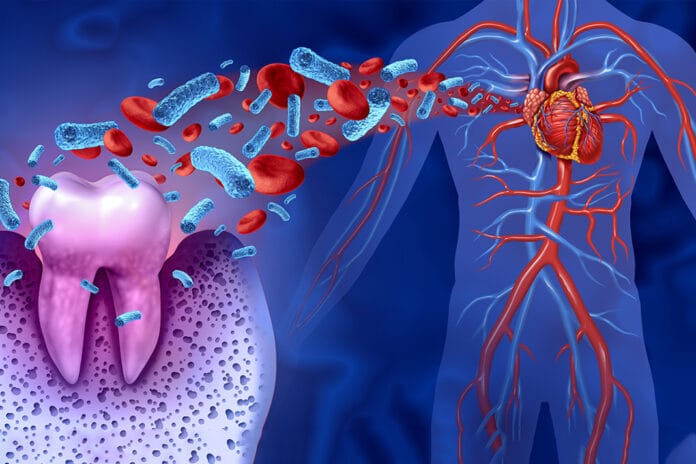

More Research Showing Relationship Between Periodontitis, Cardiovascular Disease, and Myocardial Infarction

An average of 800,000 individuals in the United States suffer from myocardial infarction yearly. Due to spiking levels in occurrence, researchers are trying to determine the...